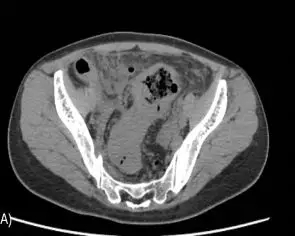

女,33岁,2017年1月9日因反复下腹疼痛2日,再发加重10小时入院,入院查体呈腹膜炎体征,中下腹可扪及约8×12cm大小质硬包块。腹部平片可见膈下游离气体(图1),CT示:乙状结肠肠壁增厚(图2),血常规:白细胞19.6 ×109/L,C反应蛋白54.9mg/L,中粒细胞分类92%,血红蛋白114.0g/L。

图2 CT提示乙状结肠壁增厚